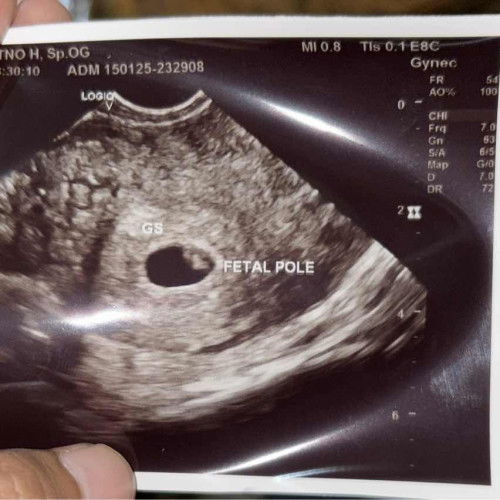

Hpht 22 november 2024

Bun , mau tanya dong 🙏🏻 Apakah ini sudah kelihatan janinnya ya ? Sempat usg beda dokter , yg 1 usg Abdomen hanya kelihatan kantung saja dan dinyatakan gugur😭 Yg ini hasil usg Transvaginal seperti ini..Masih penasaran sama hasilnya bun 🥲 #mohonbantujawabbunda #sharing #Tanya

hasil dri usg tranvagianalnya gimana bun kata dokter